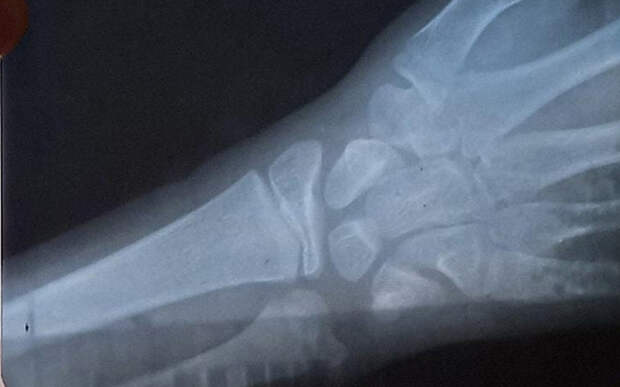

Спустя неделю, мальчику сделали рентген: отвезли в ближайший город с другой девочкой, к которой приехал папа и у которой тоже были какие-то проблемы. Но рентген ничего не показал, хотя рука болела.

6 августа школьник вернулся домой. Мама отвела мальчика в поликлинику: рентген показал несколько переломов, которые уже были запущены и не были вовремя зафиксированы для срастания. Женщина подала заявление в прокуратуру.